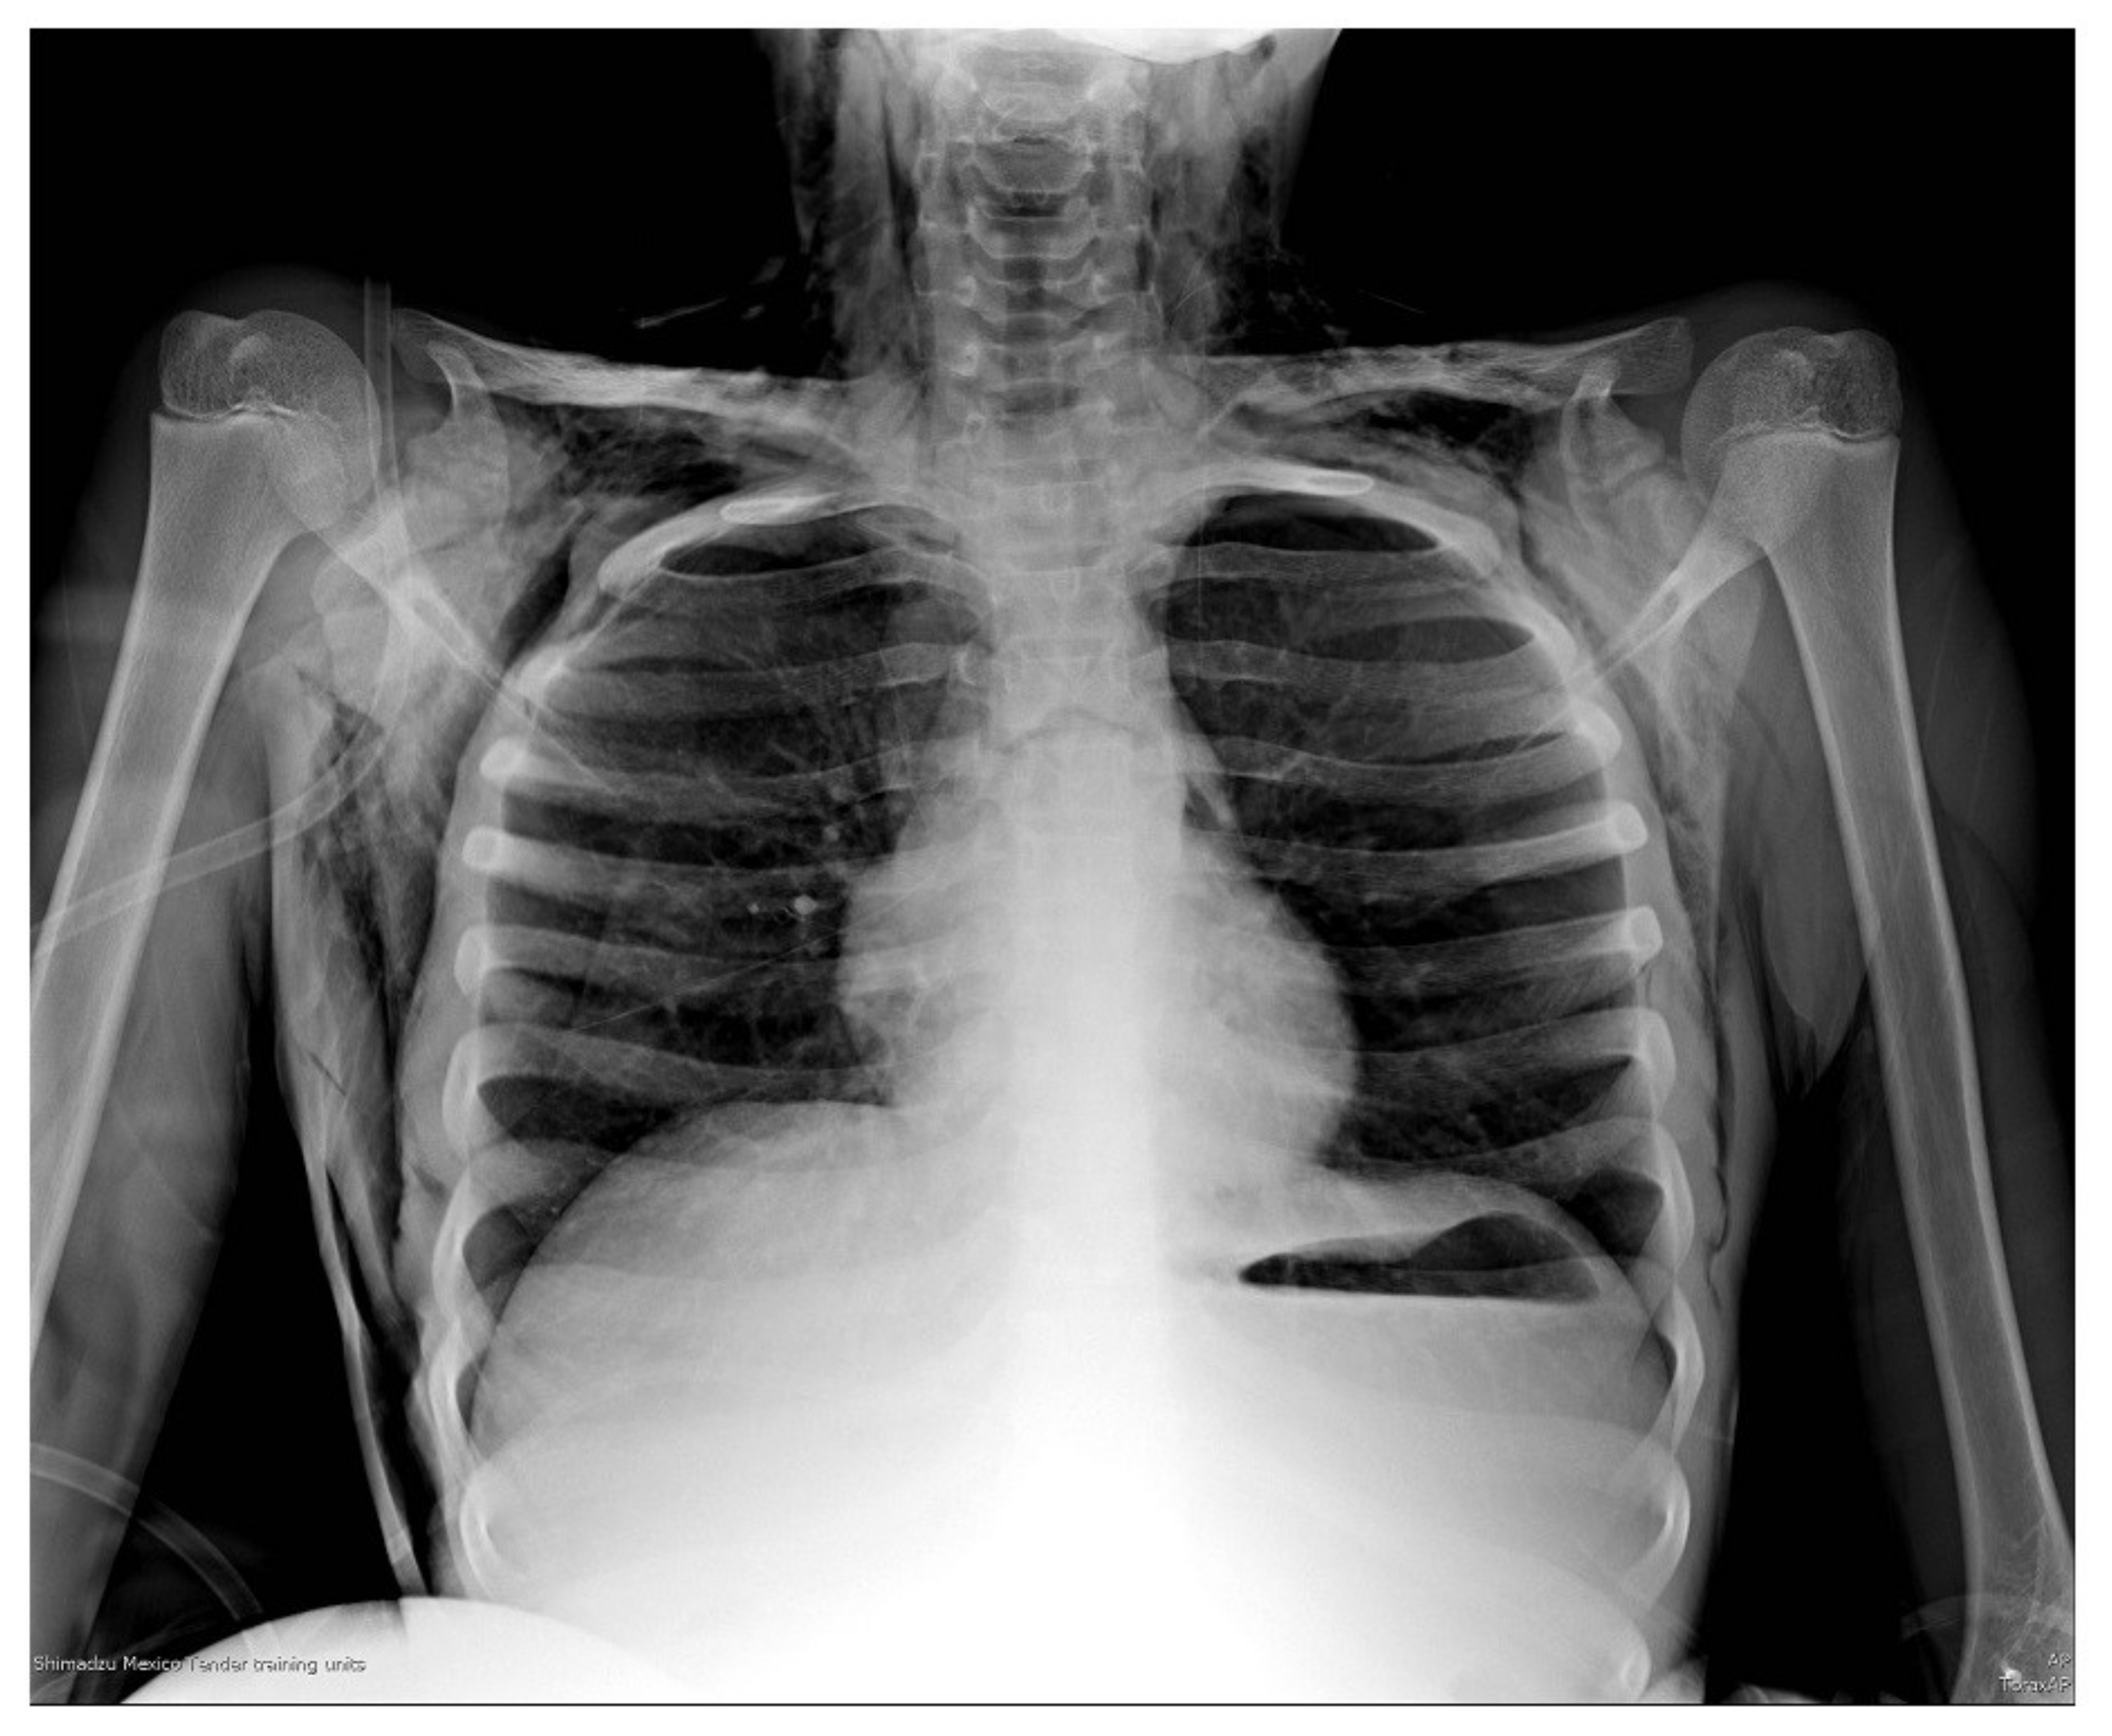

Foreign Body Aspiration X Ray

Foreign Body Aspiration X Ray Aspirated Foreign Body Foreign body aspiration occurs when a foreign body is inhaled into the airways, whereas a foreign body ingestion occurs when. It's natural for children to explore their environment by seeing, touching and tasting. Foreign body aspiration is when an object is inhaled and becomes lodged in a child’s airway or lungs. Inhalation of a foreign body into the larynx and. Aspirated Foreign Body.

Foreign Body Aspiration X Ray Aspirated Foreign Body Foreign body aspiration is the fourth leading cause of death in preschool. Foreign body aspiration occurs when a foreign body is inhaled into the airways, whereas a foreign body ingestion occurs when. Foreign body aspiration is when an object is inhaled and becomes lodged in a child’s airway or lungs. Inhalation of a foreign body into the larynx and respiratory. Aspirated Foreign Body.

Foreign Body Aspiration X Ray Aspirated Foreign Body Foreign body aspiration is when an object is inhaled and becomes lodged in a child’s airway or lungs. Foreign body aspiration occurs when a foreign body is inhaled into the airways, whereas a foreign body ingestion occurs when. An aspirated solid or semisolid object may lodge in the larynx or. Symptoms include sudden onset of respiratory distress associated. Inhalation of. Aspirated Foreign Body.

Chest X Ray Findings Of Foreign Body Aspiration And T vrogue.co Aspirated Foreign Body An aspirated solid or semisolid object may lodge in the larynx or. Inhalation of a foreign body into the larynx and respiratory tract. Foreign body aspiration is the fourth leading cause of death in preschool. Symptoms include sudden onset of respiratory distress associated. Foreign body aspiration is when an object is inhaled and becomes lodged in a child’s airway or. Aspirated Foreign Body.